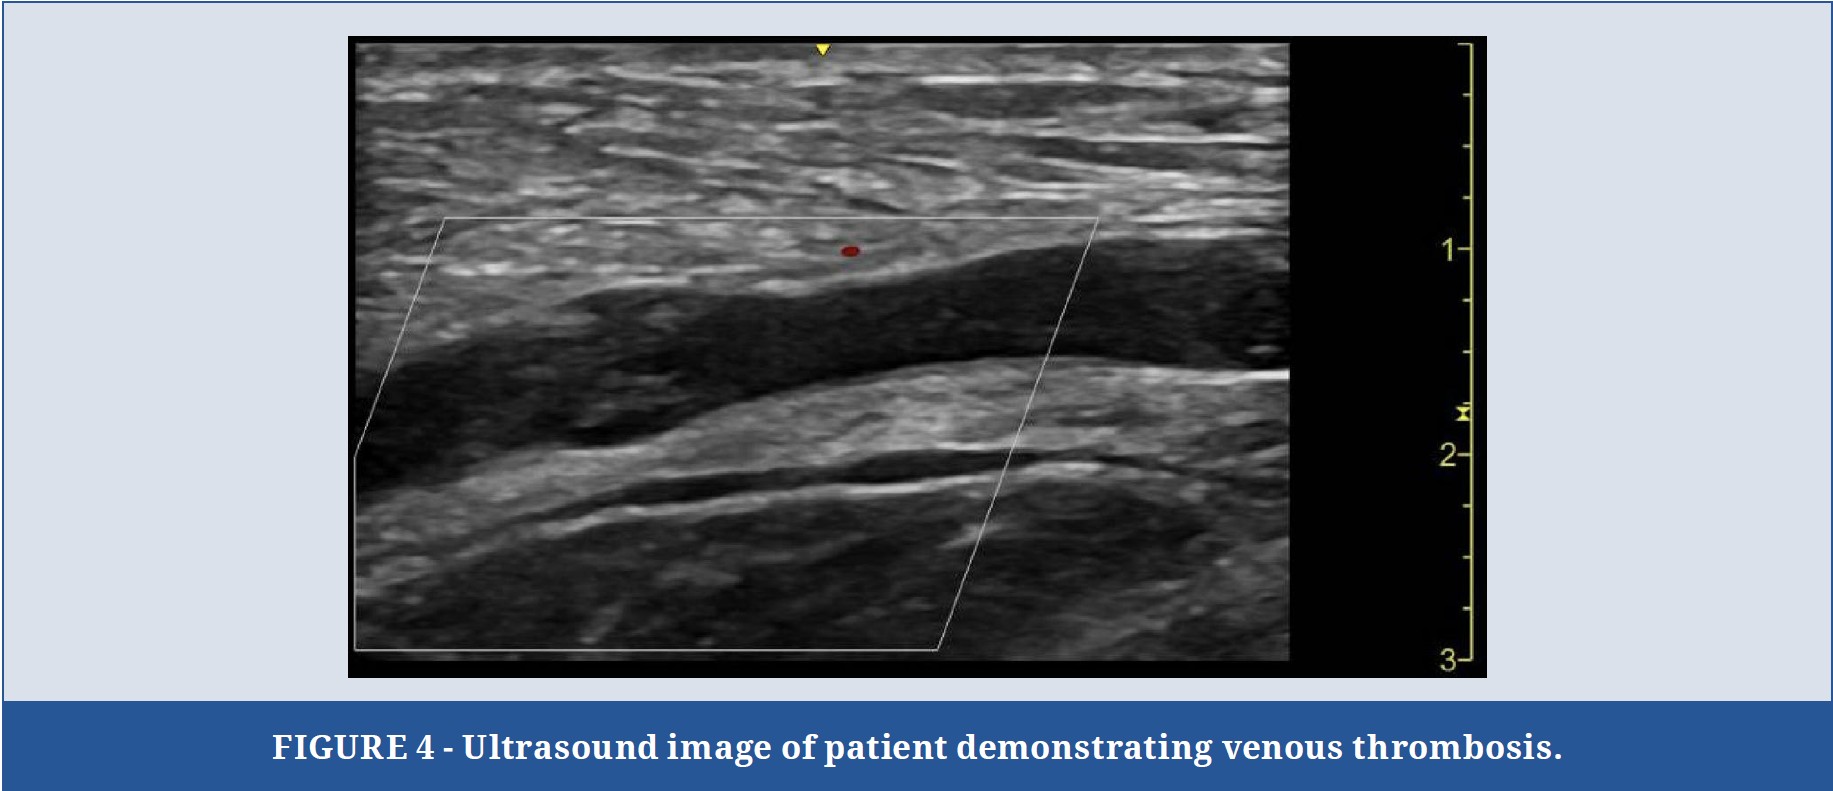

With a provisional diagnosis of sepsis, resuscitation with crystalloid intravenous fluids (NaCl) was initiated. Point-of-Care Ultrasound (PoCUS) demonstrated cobblestoning and subcutaneous air with dirty shadowing of the entire upper limb and right-side chest wall3 (Figure 3), suspicious for Necrotizing Fasciitis, as well as a non-compressible proximal part of the axillary vein suspicious for concurrent thrombus (Figure 4), likely secondary to swelling and immobility. Extended PoCUS showed a  hyperdynamic heart without effusion, LV dysfunction, or significant right heart strain.

Point-of-Care Ultrasound (PoCUS) has emerged as a valuable tool in the rapid diagnosis of Necrotizing Fasciitis, especially in the emergency department setting. PoCUS allows for bedside imaging, which can significantly reduce the time to diagnosis and subsequent treatment. In this case, PoCUS was instrumental in identifying the hallmark features of Necrotizing Fasciitis, including cobblestoning, subcutaneous air with dirty shadowing, and non-compressible veins suggesting thrombus formation7. These findings prompted immediate surgical consultation and expedited surgical intervention. The utility of PoCUS extends beyond diagnosis to include ongoing management and monitoring of disease progression. It provides real-time information about the extent of infection and can be used to guide fluid resuscitation, identify complications, such as abscess formation, and monitor the effectiveness of therapeutic interventions. Additionally, PoCUS can be used to evaluate cardiac function and detect hemodynamic instability, as was done in this case6.